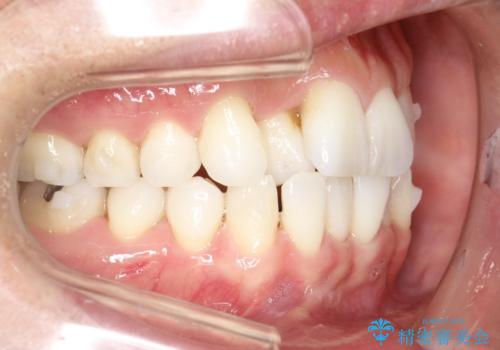

右上の前から2番目の歯が引っ込んで、下の前歯にはガタガタがありました。

上下の歯と歯の間を少量ずつ削りスペースを作り、インビザラインにて並べる計画としました。